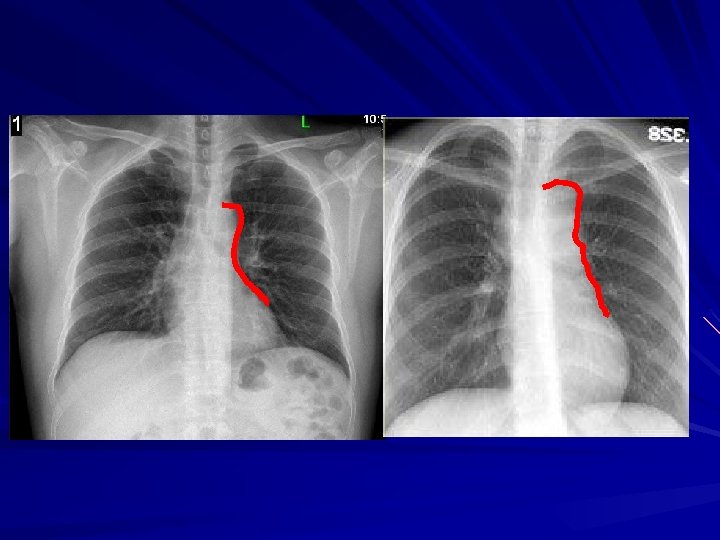

Ayakta PA akciğer grafisi Saptayabilmek için gerekli minimum miktar – 175 m. L Bazen 500 m. L sıvı bile görülemeyebilir Bulgular: – – – Diyaframın yükselmiş gibi görünmesi Kostofrenik sinüsün kapanması Menisküs bulgusu Üst kenarı konkav opasite – Masif effüzyon: Opak hemitoraks Mediastenin karşıya itilmesi – Atelektazi varsa olmayabilir

Normal kostofrenik sinüsler Küntleşmiş sinüs

Plevral effüzyon Üst kenarı konkav opasite Alt zonda, sinüsü kapatan Homojen

Plevral effüzyon miktarı ve PA grafideki görünüm 175 m. L : sinüs küntleşir – Lateral grafide 75 m. L 500 m. L: diyafram konturunu siler 1000 m. L: 4. kosta ön bölümüne yükselir

Yan grafi Görülebilirlik için en az 75 -100 m. L sıvı gerekir Bulgular: – Diyafram yükselmesi – Arka kostofrenik sinüsün homojen opasifikasyonu (üst kenarı konkav) – Diyafram konturunun silinmesi – Masif effüzyon: sadece tek diyaframın görülebilmesi Yan grafide sıvı görülmüyorsa klinik olarak önemli miktarda sıvı yok demektir

Normal Plevral effüzyon